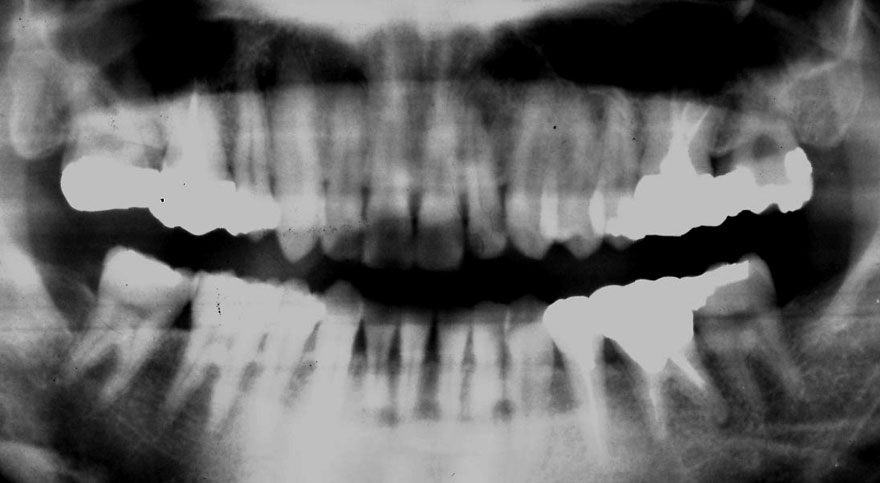

初診時 25歳 女性 平均歯槽骨喪失量:1.11mm

22年後 47歳

平均歯槽骨喪失量:1.31mm

22年間喪失量:-0.19mm

年間喪失速度:-0.009mm

(ケア頻度:2.35ヵ月ごと)